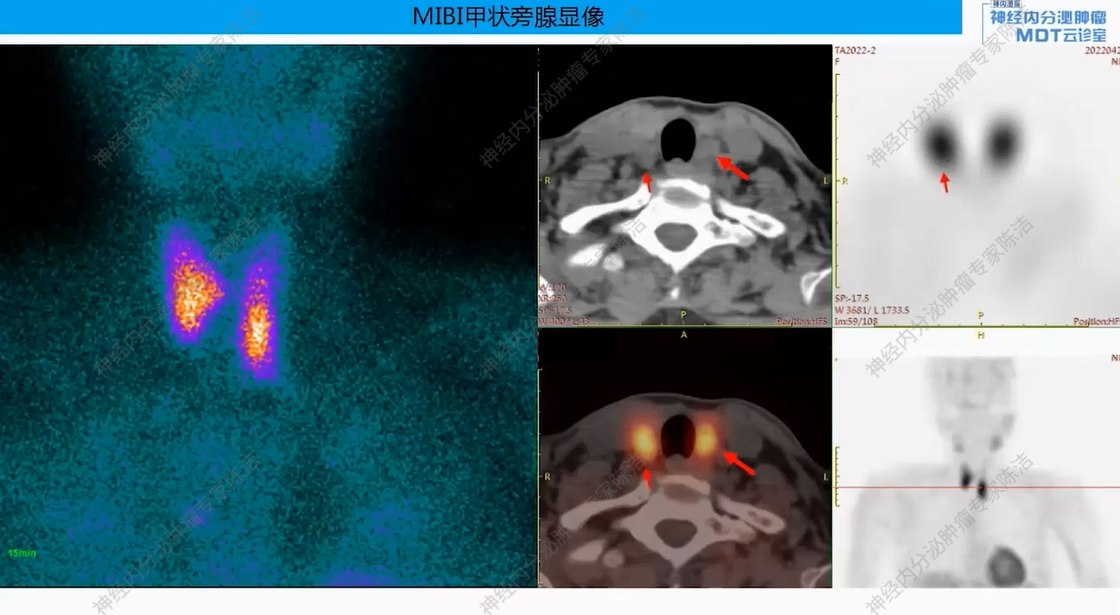

影像学:垂体MRI提示垂体稍大,最厚9mm,未见明显结节。MIBI甲状旁腺显像提示甲状腺双叶下后方软组织密度影,考虑甲状旁腺瘤,多发骨质改变。

核医学科徐俊彦教授:本病例双扫描PET显像体现了该患者多发肿瘤间异质性。胰尾大病灶(胰岛素瘤)呈SSTR阴性、FDG阳性,这符合约50%胰岛素瘤不表达SSTR的特征。而胰体小病灶呈SSTR阳性、FDG轻度增高。垂体区在SSTR(有生理性摄取)和FDG(无生理性摄取)上均呈阳性,提示垂体瘤可能。骨骼病灶呈SSTR和FDG“双阳性”,高度提示为SSTR阳性的NET转移,但建议对于骨病灶,可对相对表浅的病灶行骨穿以进一步明确骨病灶情况。从最初影像可见髂骨存在明显骨质破坏,甚至骨皮质整体受损,因此骨转移的可能性较大。然而,鉴于该患者同时患有甲状旁腺瘤,甲状旁腺瘤常伴发棕色瘤改变,故目前不能排除甲状旁腺继发的骨改变的可能。

头颈外科王宇教授:在甲状旁腺病灶的处理上,该患者表现出较高的PTH水平(2200+),但术后血钙水平持续正常(约2.4 mmol/L)。怀疑临床检测到的高水平PTH可能是无生物活性的激素片段,而非全长的活性PTH。也可能是患者使用双磷酸盐后高钙血症得以控制。因此,患者虽然有甲状旁腺瘤,但目前血钙正常,可暂不对甲状旁腺进行手术干预。

后续治疗需要明确多发骨质改变的性质,建议对骨病灶进行穿刺活检。此举旨在鉴别其究竟是SSTR阳性的NET骨转移,还是甲状旁腺病变相关的骨病。若证实为SSTR阳性的NET转移,可考虑使用小剂量长效生长抑素类似物进行治疗。若证实为甲旁亢相关骨病,或活检未见肿瘤细胞,则无需使用生长抑素类似物。关于甲状旁腺处理,患者目前无明显血钙升高,可暂不手术,密切随访血钙、PTH变化。对于垂体处理,建议完善垂体薄层动态增强MRI以明确诊断,并评估对周围组织器官压迫情况。